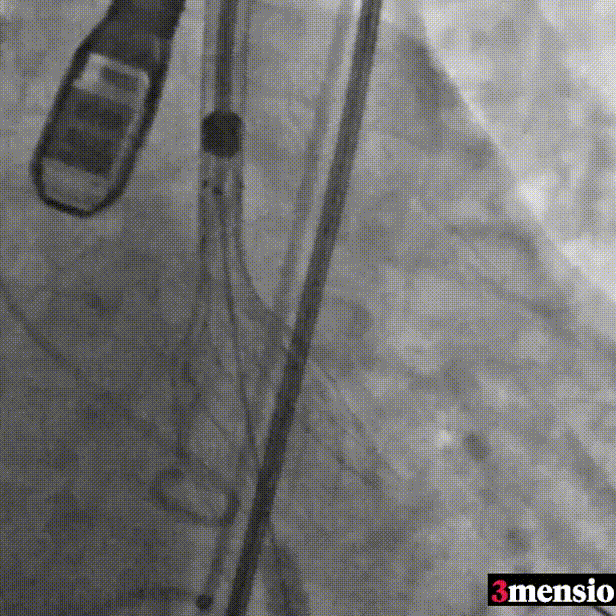

术后即刻评估

术后压差从108mmHg降至6.84mmHg,无瓣周漏,瓣膜正常工作,血流动力学即刻得到改善。